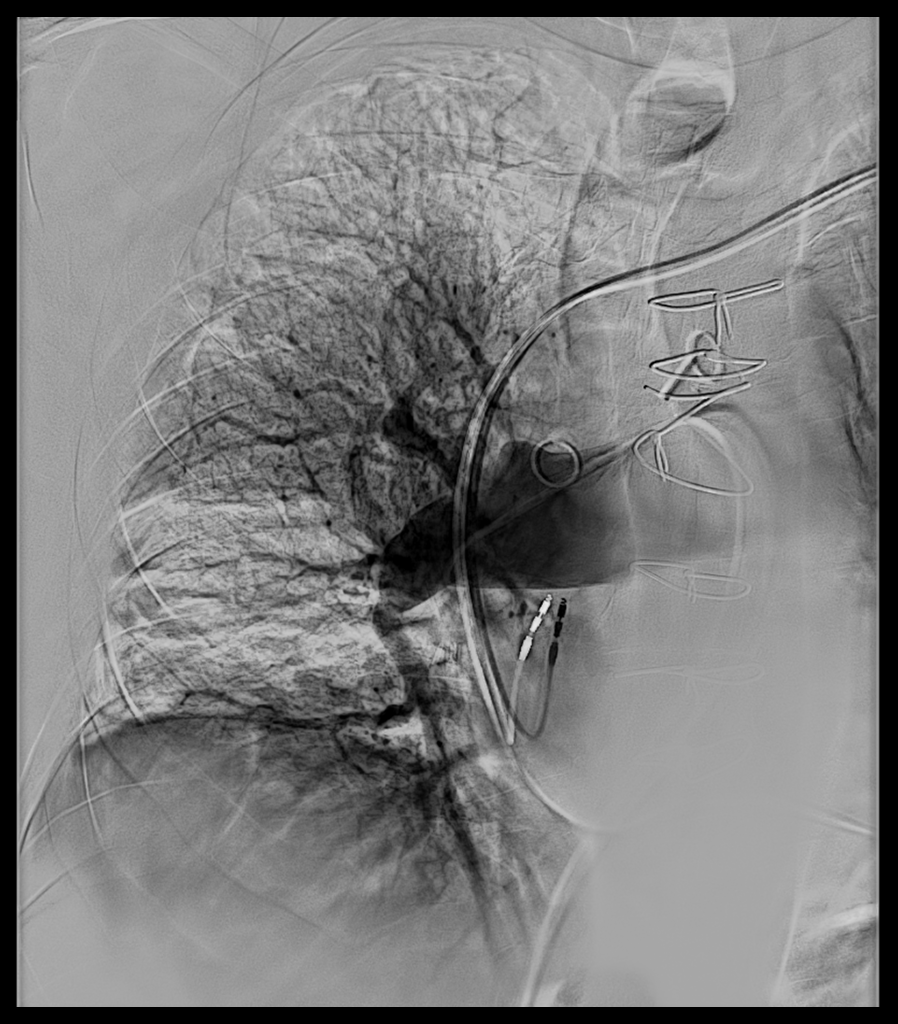

This image shows the catheter entering from the top right to inject dye into Dan Dudley's right lung to confirm his diagnosis.

Dr. Bartolome and her team performed a series of assessments to confirm the diagnosis and determine whether Dan would be a suitable candidate for surgery. This included computed tomography angiography (CTA), echocardiography, ventilation/perfusion scanning, a right heart cardiac catheterization with pulmonary angiography, and multiple lung and heart function tests. Using these tests, doctors are looking for red flags, such as enlarged heart chambers, backflow of blood, and pressure in the pulmonary blood vessels.

Dan’s lung images showed large scarred-in blood clots, and his echocardiogram indicated the blood pressure in his lungs was double what it should be. As a result, he had poor function on the right side of his heart, and the distance he could walk comfortably was cut in half.